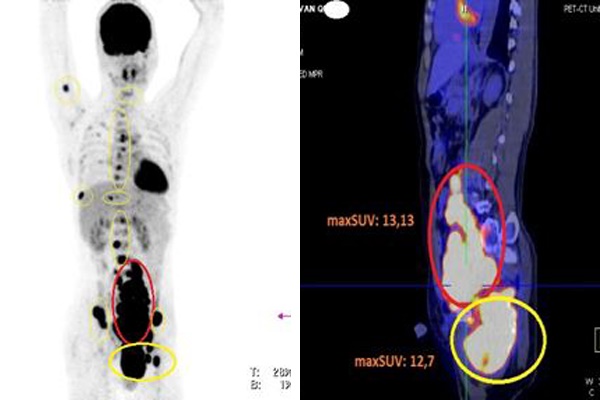

Hình ảnh PET/CT cho thấy bệnh nhân có nhiều hạch khắp cơ thể, các hạch tăng hấp thu FDG (vòng tròn màu đỏ), các tổn thương xương tăng hấp thu FDG (vòng tròn màu vàng)

Tiếp tục chỉ định chụp PET/CT toàn thân để đánh giá các tổn thương và giai đoạn bệnh, bác sĩ phát hiện ổ bụng có rất nhiều hạch dọc cơ thắt lưng chậu, hạch hố chậu trái, nhiều hạch bẹn trái, hạch kích thước lớn nhất tương đương quả trứng gà.

Ngoài ra, bệnh nhân có nhiều ổ tổn thương ở xương sọ, đốt sống cổ C2, các đốt sống ngực D4, D5, D7, D8, D12; các đốt sống thắt lưng L2, L4; xương cùng S1; xương cánh chậu phải, tủy xương cánh tay phải; xương sườn số 9; xương đòn phải; xương ức; tổn thương xương chậu trái có khối xâm lấn cổ xương đùi trái và phần mềm xung quanh, kích thước 13,3x8,1 cm.